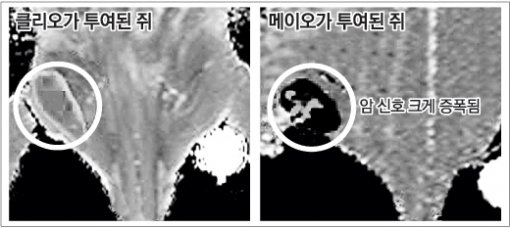

연구팀은 유방암과 난소암에 걸린 실험용 쥐의 혈관에 메이오를 주입하고 암세포를 MRI로 촬영했다.

그 결과 2mm 크기의 아주 작은 초기 암세포까지 선명하게 나타났다. 기존 MRI 사진에서는 암이 상당히 진행된 뒤에야 암세포를 선별해 낼 수 있다.

메이오가 온몸을 돌아다니며 암세포를 정확하게 찾아내 달라붙으면 MRI 장비가 메이오의 자성을 감지해 영상신호가 증폭되는 원리다.

천 교수는 “미국 하버드대에서 개발한 최신 나노 입자인 ‘클리오(CLIO)’보다 메이오를 이용했을 때 MRI 신호가 10배가량 더 강해졌다”며 “임상시험을 거쳐 실용화되면 조기 암 진단에 획기적인 진전을 가져올 수 있을 것”이라고 말했다.